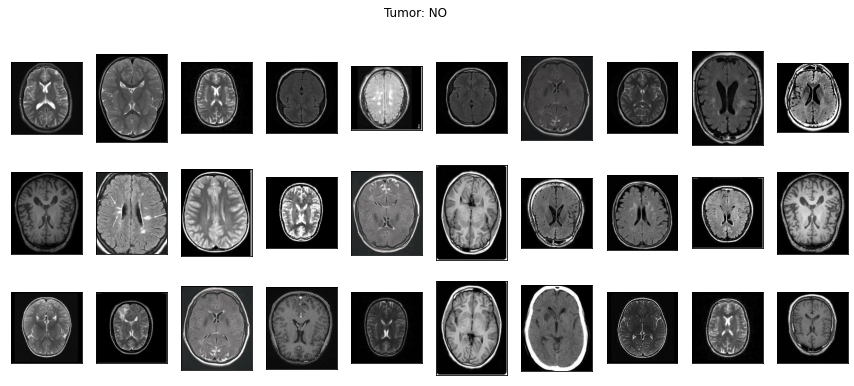

아울러 일반적인 사진 이외에 의료영상도 이미지 분석이 가능해요. 의료영상은 DICOM(Digital Imaging and Communications in Medicine) file(확장자 .dcm)로 저장되어 있어요. 'Digital' 즉, 숫자 형식으로 되어있기에 이미지 분석이 가능해요. 아래의 이미지는 뇌종양을 진단하기 위한 MRI 이미지예요!

이 이미지를 이용해서 뇌종양을 예측하는 알고리즘을 아래에서 실습해볼테니 끝까지 봐주세요!

네! 위에서 보았던 뇌종양 양성과 음성의 MRI 이미지 데이터로 뇌종양 진단을 한다면 아래와 같이 할 수 있어요.

양성 1500개, 음성 1500개인 균등한 데이터를 준비해서 <Image Reader>로 읽었어요. ‘yes’ 주석이 있는 윗줄이 양성 이미지이고 ‘no’ 주석이 있는 아랫줄이 음성 이미지에요.